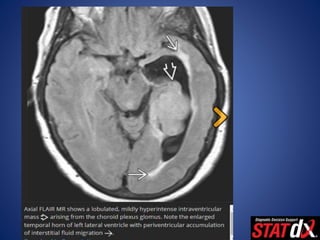

• Arises from arachnoid cap cells with some probable

contribution from dural fi broblasts and pial cells.

• It is believed that intraventricular meningiomas arise

from arachnoidal cap cell rests buried within the

choroid plexus.

Pathology • Arises fromarachnoid cap cells with some probable contribution from dural fi broblasts and pial cells. • It is believed that intraventricular meningiomas arise from arachnoidal cap cell rests buried within the choroid plexus.